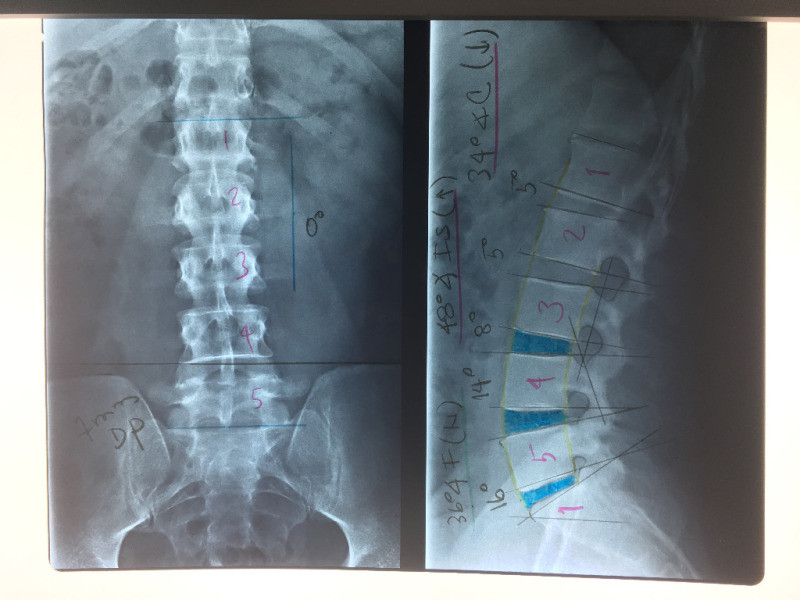

Artroplastía lumbar y prótesis de columna

Envíado por Dr. Hugo Enrique Castro Cordero